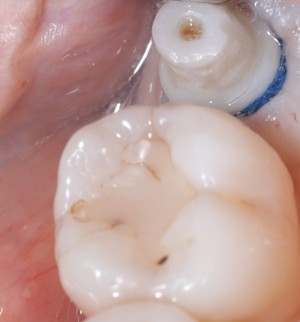

Prosthodontics (also known as dental prosthetics or prosthetic dentistry) is one of the nine dental specialties recognized by the American Dental Association (ADA). Prosthodontists specialize in the diagnosis, restoration, and replacement of missing teeth.

Extensive training and experience give prosthodontists a unique understanding of restoring the dynamics of a smile and healthy mouth with the creation of tooth prostheses. Becoming a prosthodontist requires an additional three years of specialty training after obtaining a DMD (Doctor of Dental Medicine) or DDS (Doctor of Dental Surgery) degree.